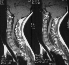

A condition which is defined by a tubular cavity which contains fluid within the spinal cord.

Rapidly progressive scoliosis, Upper thoracic curve, Left thoracic curve, High double thoracic curve, Cervical bony , nomalies, Erosion of cervical bodies, Widened spinal canal, Basilar invagination, Cervical ribs

Suspect if C5 canal is 6mm greater than body. If it is 4mm there is a 3:1 probability of syrinx.

If C5 canal is wider than C6 body - suspect.